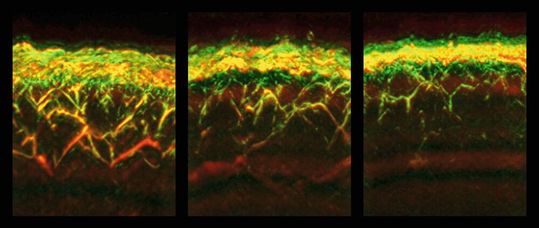

RSOM-Aufnahmen von Haut eines gesunden Probanden (links), eines Patienten mit Diabetes (mitte) und eines Patienten mit Diabetes und Neuropathie (rechts).(Bild:  Nikoletta Katsouli / TUM)

RSOM-Aufnahmen von Haut eines gesunden Probanden (links), eines Patienten mit Diabetes (mitte) und eines Patienten mit Diabetes und Neuropathie (rechts).

Mit einer einzigen RSOM-Messung können gleichzeitig Daten aus verschiedenen Hautschichten gewonnen werden. So konnten die Forschenden erstmals feststellen, dass Diabetes die Gefäße in verschiedenen Hautschichten unterschiedlich beeinflusst: Während beispielsweise die Zahl der Gefäße und Verästlungen in der dermalen Ebene bei Diabetikern verringert war, waren sie dichter unter der Hautoberfläche, in der epidermalen Ebene, erhöht.